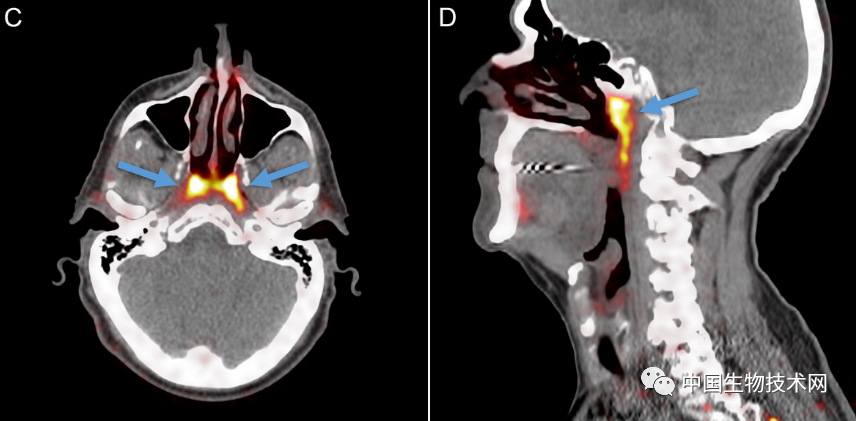

在对所有100例患者进行的PSMA PET/CT扫描,均发现存在这些管腺,并且对两名尸体(一男一女)的身体检查也显示出神秘的双侧结构,从宏观上可见引流管开口朝向鼻咽壁。

研究人员在他们的论文中解释道:“据我们所知,这个结构并不符合之前的解剖学描述。据推测,它可能含有大量的浆液腺泡,对鼻咽/口咽润滑和吞咽起到生理作用。”

至于这些腺体是如何被识别出来的,研究人员表示,“管状腺”是在颅底一个不易接近的解剖位置被发现的,用内窥镜是很难辨认出来的,因为它们是一个更大腺体系统的一部分。此外,只有更新的PSMA-PET/CT成像技术才能检测到新唾液腺的结构,这超出了超声波、CT和MRI扫描等技术的可视化能力。